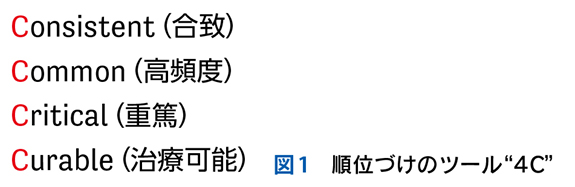

▶ 症例によっては,ここまで述べたような条件を満たす問題を複数定義できることがある。この場合は,それぞれの問題が描くフレームが重なり合うところに診断があると考えるとよい(図3)。

▶ 再びNew England Journal of Medicine誌上の症例検討3)を例として挙げる。40歳代男性が急性多関節炎,下腿の結節性紅斑,両側肺門部リンパ節腫脹を呈したケースである。これら3個の問題の組み合わせは,知っていればLöfgren症候群というサルコイドーシスの1病型と「スナップ診断」できるが,この知識がなくてもフレームの重ね合わせで診断に至ることが可能である。

▶ これらの問題はそれぞれが比較的high yieldであり,よいフレームとなりうる。3つのフレーム内でそれぞれ網羅的に鑑別を挙げ(その方法はステップ②で後述),重なるところに着目するとサルコイドーシスが診断の第一仮説に浮上する。ちなみにこのケースでは患者は発熱と失神も呈しているが,発熱はlow yieldであり鑑別を減らすのに役立たず(急性多関節炎,結節性紅斑,肺門部リンパ節腫脹を呈する疾患はほぼすべて発熱を呈してもおかしくない),失神はこのケースでは最終的に(心サルコイドーシスに起因するものではなく)発熱下での神経調節性失神という評価となり,サルコイドーシスの診断においてはノイズだった(二元論で説明される症状だった)ことがわかる(図7)。